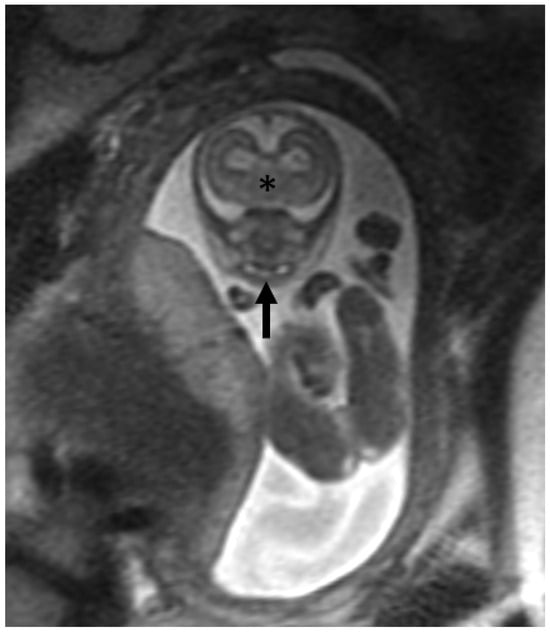

- Kunzendorf, B.; Diogo, M.C.; Covini, D.I.; Weber, M.; Gruber, G.M.; Zeilhofer, H.-F.; Berg, B.-I.; Prayer, D. Comparison of the Visibility of Fetal Tooth Buds on 1.5 and 3 Tesla MRI. J. Clin. Med. Res. 2020, 9, 3424. [Google Scholar] [CrossRef]